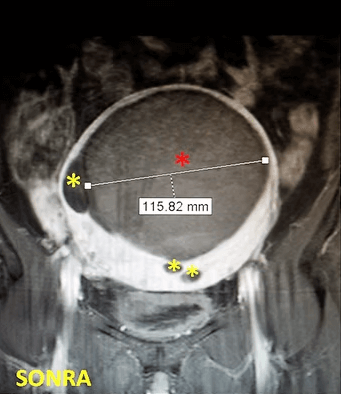

37 yaşında, kansızlık, gaz, sık idrara çıkma şikayetleri ve hamilelik arzusu var. Miyomektomi önerilmiş, ancak operasyonda rahimin alınabileceği söylenmiş. Emar’da tek, dev bir miyom (*) mevcut. Tek seans perkütan ablasyon sonrası miyomun belirgin küçüldüğü izleniyor. İşlemden 2 yıl sonra hasta hamile kalmıştır.